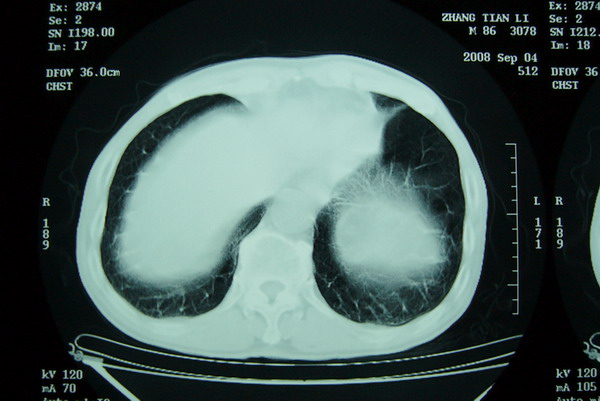

标题: CT15579:男 86岁 咳嗽 咳少量白痰 发热2天 吸烟史60年 [打印本页]

标题: CT15579:男 86岁 咳嗽 咳少量白痰 发热2天 吸烟史60年

右上周围型肺癌,慢支,肺气肿。

右上肺一不规则团块,边缘有分叶和毛刺,纵隔有淋巴结肿大。右肺周围性肺癌首先考虑。